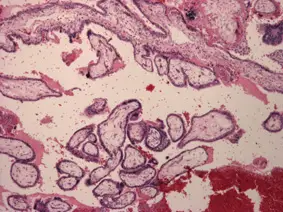

一位 30歲女性,因下腹痛來急診,身體檢查發現病人血壓過低,緊急開刀發現右側輸卵管有血塊。病理檢查發現如下圖的構造,最可能的診斷是:

顯微鏡下圖片(H&E 染色,低倍)顯示:

- 主要結構:大量形態規則的分支狀絨毛膜絨毛(branching chorionic villi),絨毛外形輪廓清晰,呈樹狀分支結構。

- 絨毛特徵:絨毛間質(villous stroma)呈水腫疏鬆狀,但無顯著的囊性膨大(cistern formation),無完全水泡狀胎塊所見的極度腫大絨毛。

- 滋養層細胞:絨毛表面可見細滋養層(cytotrophoblast)和合體滋養層(syncytiotrophoblast),無顯著異型增生。

- 背景:大量紅血球(hemorrhage),符合輸卵管破裂出血的背景環境,可見纖維性組織(推測為輸卵管壁)。

- 無壞死性增殖:無大片無絨毛核碎片增生,排除絨毛癌(choriocarcinoma)。

上述組織學形態符合**子宮外孕(輸卵管妊娠)**的病理表現:輸卵管內可見形態正常的絨毛膜絨毛與滋養層細胞,伴隨出血背景,